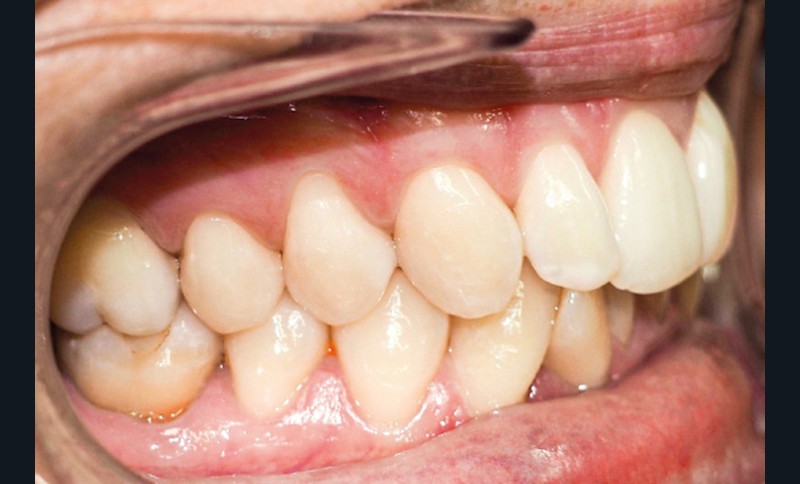

Discussion (fig. 4 à 7)

La durée du traitement a été de vingt-trois mois. Des mouvements lents ont permis un contrôle des axes incisifs mandibulaires.

Le stripping maxillaire a permis :

- de rééquilibrer les dimensions entre les incisives centrales et latérales (DDD initiale par insuffisance maxillaire) ;

- d’éviter l’apparition de triangles noirs entre les incisives [3] ;

- d’éviter la présence d’un surplomb résiduel.

Des triangles noirs sont apparus à la mandibule suite à l’extraction de 31 : ils ne sont pas exposés lors du sourire, ce qui n’entraîne pas de défaut esthétique.

La génioplastie discrète apporte un équilibre facial et une fermeture labiale non forcée, ce qui limite le risque de récidive liée à la pression musculaire.

La superposition des structures anatomiques nous montre une ingression de l’incisive mandibulaire et un maintien de l’axe ainsi qu’une distalisation en gression de l’incisive maxillaire.